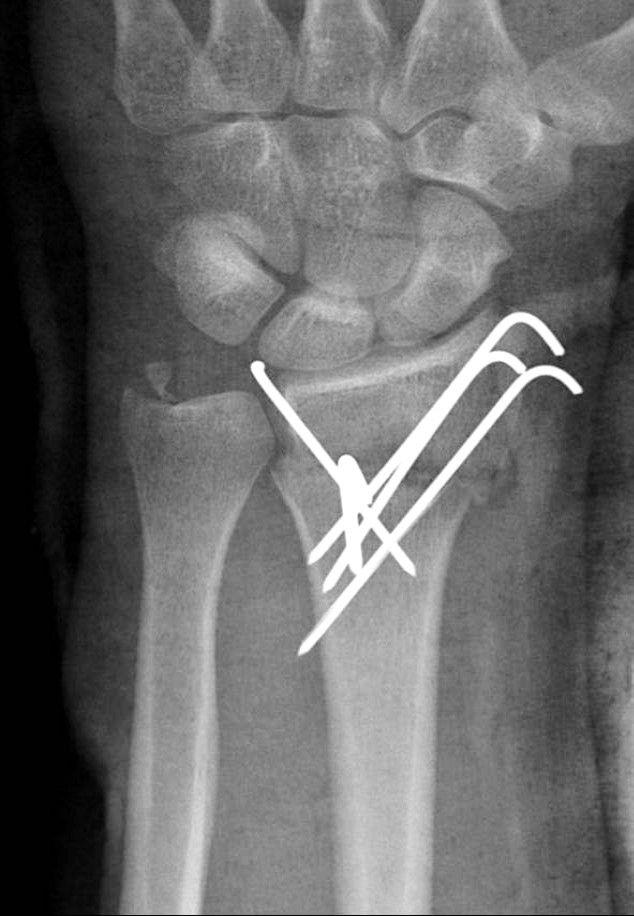

Hsu LP, Schwartz EG, Kalainov DM, Chen F, Makowiec RL. Complications of K-wire fixation in procedures involving the hand and wrist. J Hand Surg Am 2011;36(4):610-6.

Subramanian P, Kantharuban S, Shilston S, Pearce OJ. Complications of Kirschner-wire fixation in distal radius fractures. Tech Hand Up Extrem Surg 2012;16(3):120-3.

Abul A, Karam M, Al-Shammari S, Giannoudis P, Pandit H, Nisar S. Peri-operative antibiotic prophylaxis in K-wire fixation: a systematic review and meta-analysis. Indian J Orthop 2023;57(7):1000-7.

Ridley TJ, Freking W, Erickson LO, Ward CM. Incidence of treatment for infection of buried versus exposed Kirschner wires in phalangeal, metacarpal, and distal radial fractures. J Hand Surg Am 2017;42(7):525-31.

Lakshmanan P, Dixit V, Reed MR, Sher JL. Infection rate of percutaneous Kirschner wire fixation for distal radius fractures. J Orthop Surg (Hong Kong) 2010;8(1):85-6.